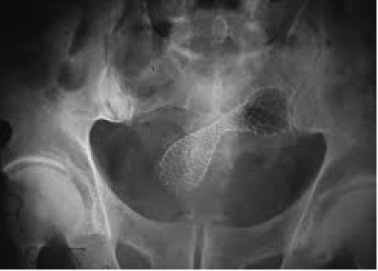

Las prótesis, que son pequeños tubos que permiten abrir la zona obstruida, pueden ser de metal o de plástico. Existen diversos modelos, las constituidas de ligas metálicas como Elgiloy (cobalto y cromo), Nitinol (niquel y titanio) y acero inoxidable, disponibles en varios tamaños, formas, revestidas o no. Las prótesis van montadas en un catéter (tubo fino) y sujetas con un hilo, y el principio de la colocación se basa en la transposición de la obstrucción a través de una guía, sobre la cual será pasado el sistema de introducción con la prótesis en la forma restringida. Posterior a la ubicación adecuada abarcando toda la estenosis, se libera la prótesis permitiendo su expansión y posteriormente el sistema introductor es retirado.

El proceso se realiza bajo control endoscópico y radiológico y con el paciente bajo sedación profunda.